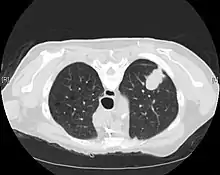

CT imaging provides better evaluation of the lungs, with higher sensitivity and specificity for lung cancer compared to chest radiograph (although still significant false positive rate[25]). Computed tomography (CT) that is specifically aimed at evaluating lung cancer includes the chest and the upper abdomen. This allows for evaluation of other relevant anatomic structures such as nearby lymph nodes, adrenal glands, liver, and bones which may show evidence of metastatic spread of disease.[4] Indeed, the US Preventative Services Task Force recommends annual screening with low-dose CT in adults aged 55 to 80 years who have a 30 pack-year smoking history and currently smoke or have quit within the past 15 years, with certain caveats (see Lung cancer screening).[26]